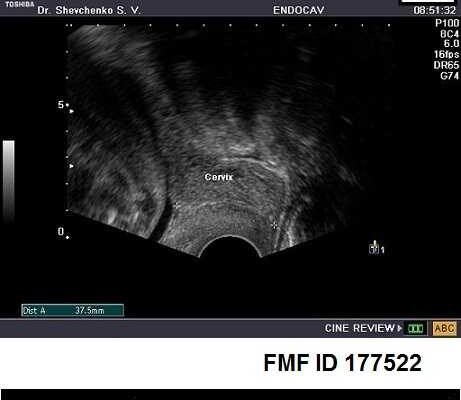

Цервікометрія при вагітності: норма Цервікометрія при вагітності – що це таке? Норма цього параметра має величезне значення для майбутніх мам.